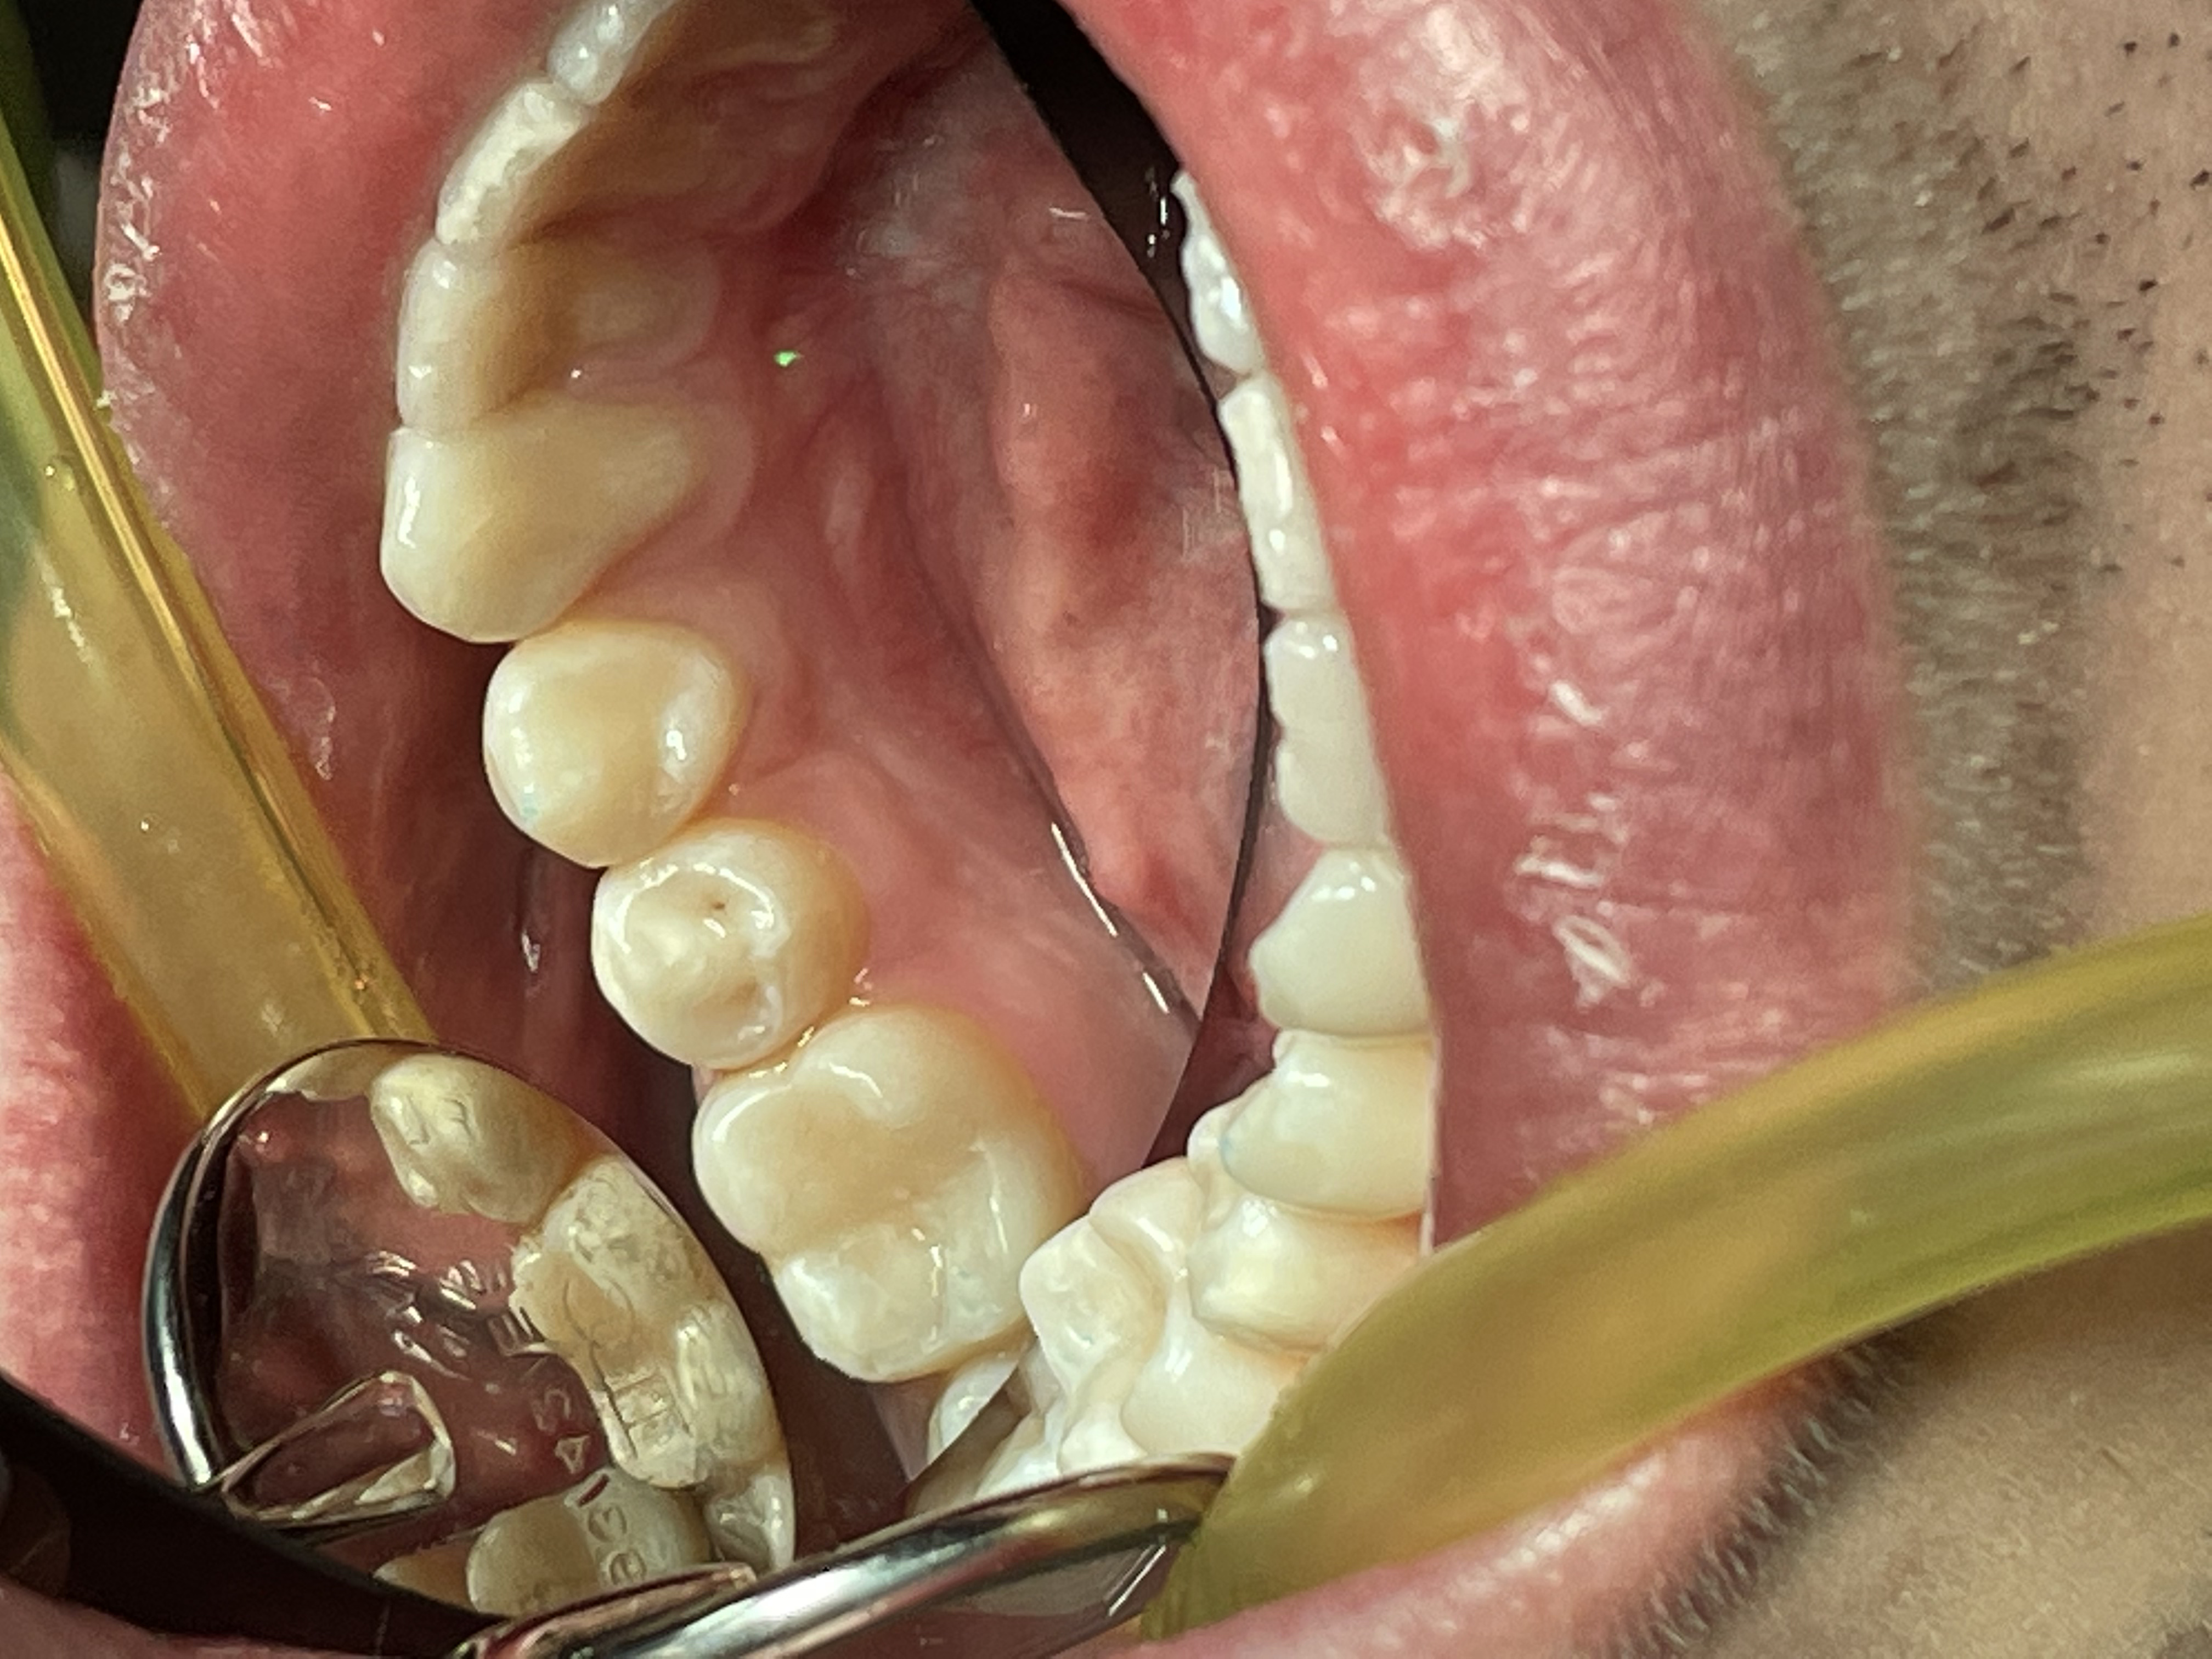

В данной работе на фото достигнута глубина полимеризации микрогибридного Японского композита при помощи диодных, поливалентных фотополимеризаторов без нагревания.

6 этап - Наслоение композита, техника гиперхроматичемкой композитной реставрации жевательных зубов.

5 этап- Контроль качества без микротрещин и подтеканий.